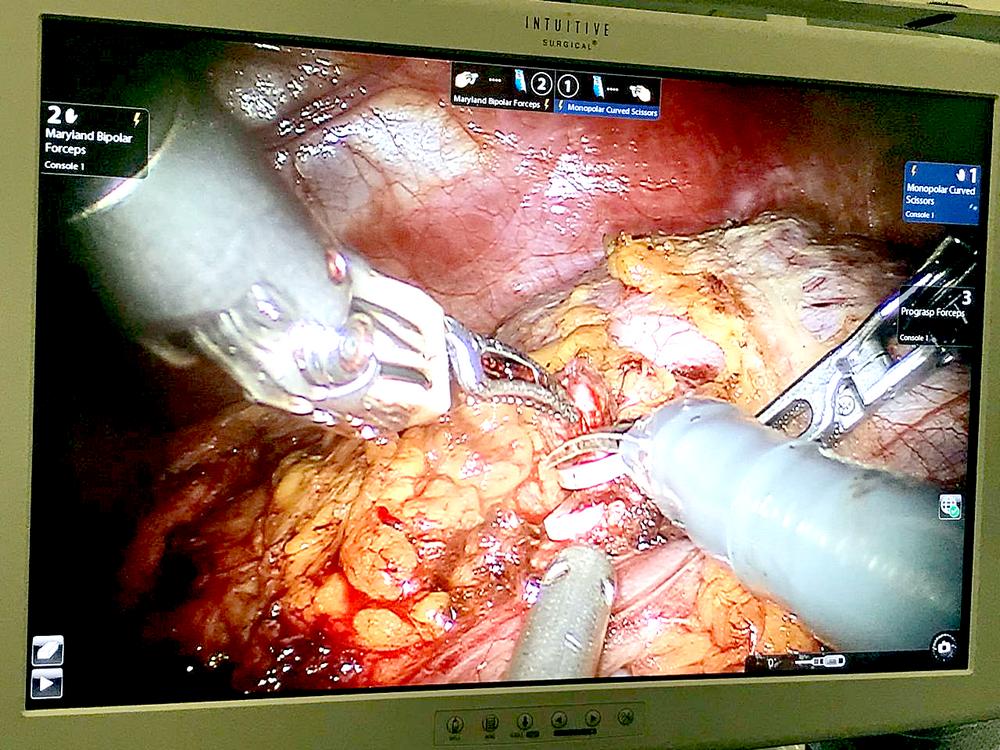

В Центре Алмазова успешно проведена первая в России робот-ассистированная операция по устранению аневризмы левой почечной артерии и билатерального стеноза почечных артерий.

Выполнил операцию заведующий кафедрой урологии лечебного факультета Института медицинского образования Центра Алмазова, д.м.н. М. С. Мосоян.

В операционной за состоянием пациентки наблюдали сосудистый хирург, врач-кардиолог, а также специалист в области реноваскулярной артериальной гипертензии. Хирургическое вмешательство прошло успешно, без осложнений, а также без нарушения почечного кровотока и ишемии почки.

Операция, выполненная 34-летней пациентке, стала первым этапом в комплексном хирургическом лечении. В дальнейшем планируется выполнение второй части — баллонной пластики стеноза левой почечной артерии.